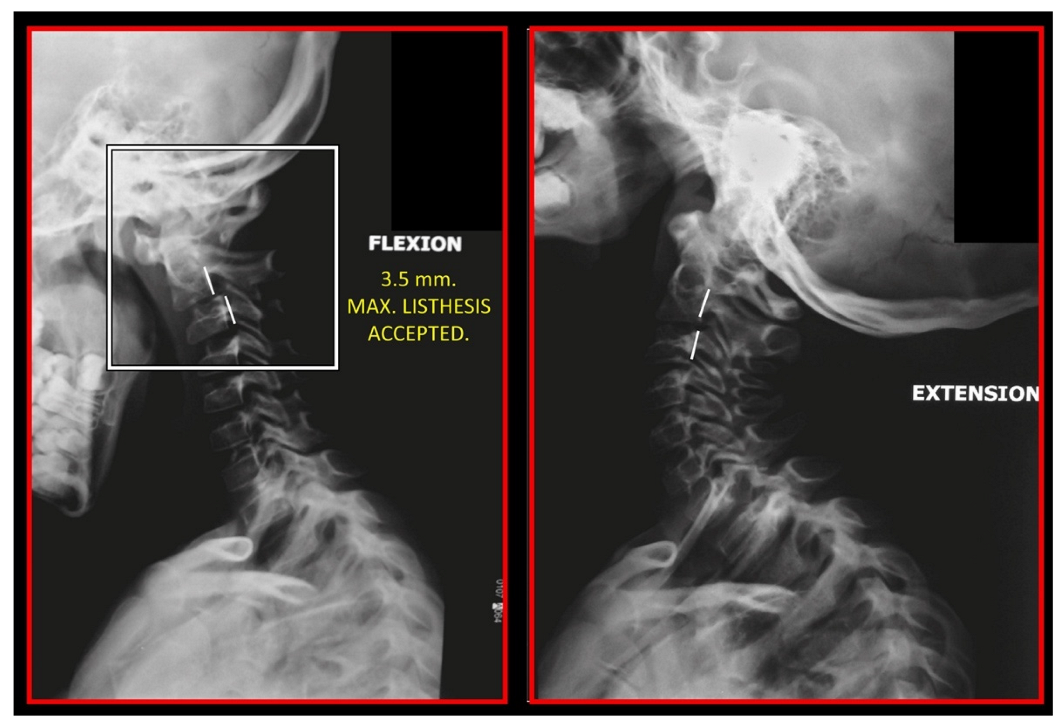

10.1. Neck X-ray

11.5. Axis and Atlas Derotation